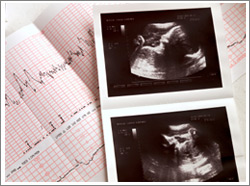

Schwangerschaft

- Schwangerschaftsbetreuung: Ultraschall, Mutter-Kind-Pass Untersuchungen